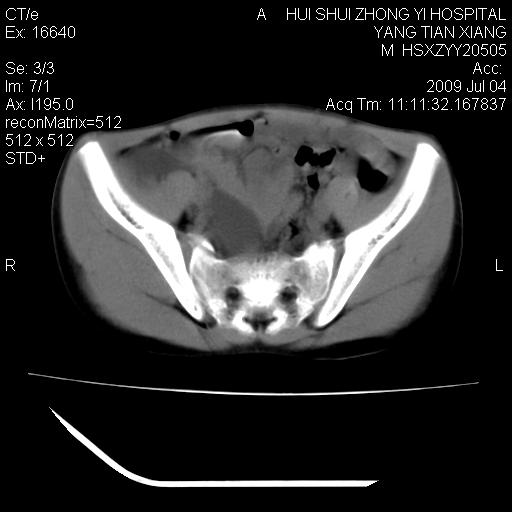

肝右叶胆管内见条状高密度影,脾脏增大,双肾上腺无异常;右肾正常结构消失,其实质内见类圆形低密度灶,ct值范围0-6hu,界清,右输尿管全程伴行多发低密度灶,界清,膀胱壁增厚,腹盆腔未见确切肿大淋巴结。

考虑:1、肝内多发胆管结石并肝内胆管扩张。2、右肾、输尿管多发脂肪瘤,多发平滑肌瘤?建议ct增强检查。4、膀胱壁增厚。

1)考虑右侧巨输尿管畸形。2)肝内胆管多发性结石。3)脾大。

右侧巨输尿管并神谕积水,左肾代偿性肥大,脾大,肝内胆管多发结石并胆管扩张。